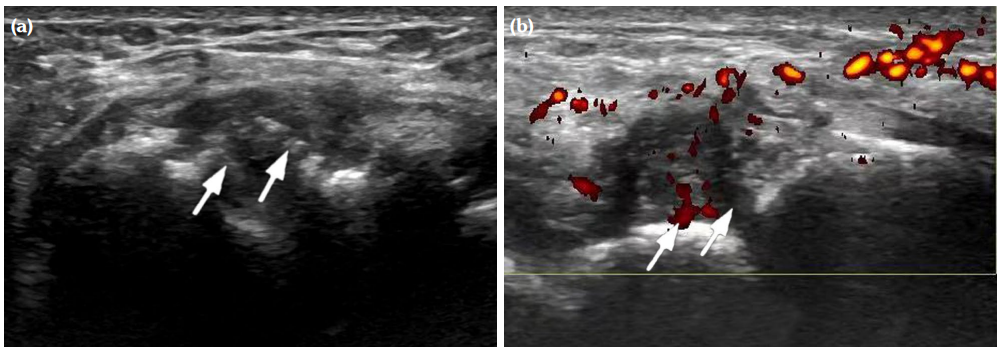

The degree of BE and synovial hyperplasia in SNRA or SPRA is more serious, and the blood flow signal is more abundant. However, the degree of synovial hyperplasia in osteoarthritis was mild, and no obvious blood flow signal was detected (Figures 1, 2, 3 and 4). Magnetic resonance imaging (MRI) studies of SPRA also showed serious BE (Figure 5).

Among SNRA, SPRA and non-RA, there was no significant difference in the grades of SH, PD, BE, nor the number of cases of tendinitis and tenosynovitis between the SNRA group and the SPRA group (p>0.05) (Table 3). There were, however, statistically significant differences in the number of cases of SH1, SH3, PD and BE grades between the SNRA and non-RA groups (p<0.001). There was no significant difference in the number of cases of SH2, PD2, tendinitis or tenosynovitis between the SNRA and non-RA groups (p>0.05) (Table 4).

Our findings suggest that the use of synovial blood flow and the degree of BE are helpful in distinguishing RA from non-RA, which may be explained by the underlying pathological changes. The pathological features of RA include primary synovial inflammation, which produces aggressive synovial pannus attached to the cartilage, causing hypoxia and erosion of the bone. Synovitis caused by non-RA disease is mostly due to inflammation, edema and thickening of synovium due to degenerative or pathological changes of cartilage and cortical bone. It is not difficult to understand that the invasive synovial blood vessels during RA are closely related to the phenomenon of BE; thus, the combination of the two ultrasonic characteristics are sound pathological indicators for the evaluation of RA.